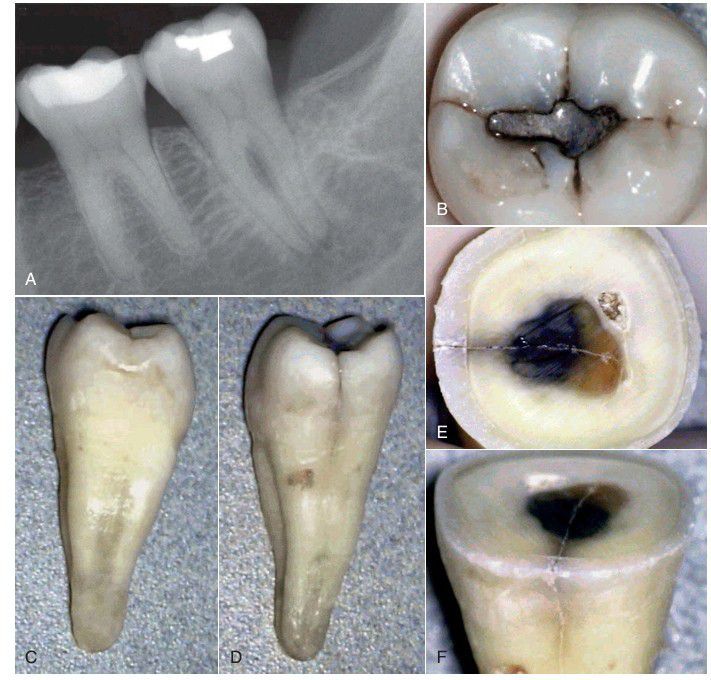

A tooth with minimal or no restoration or caries is unlikely to become nonvital. A, This radiograph of a mandibular second molar shows a restoration that is distant from the pulp chamber, yet the tooth is nonvital and symptomatic. B, On occlusal examination, a slight crack is observed on the distal marginal ridge. C, After extraction, the mesial aspect of the crown and root shows no indication of a fracture. D, However, the distal aspect of the crown and coronal root shows the fracture. E and F, When the crown is sectioned, the crack can be observed to extend well into the pulp chamber.